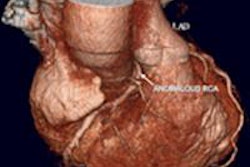

Above, an adult with a left atrial thrombus that was unreported on echocardiography and seen on CT as a filling defect on the arterial (red arrow) and delayed (orange arrow) enhancement phases. Below, an adult with remote inferior myocardial infarction that was unreported on echocardiography and seen on CT as left ventricular inferior myocardial thinning (red arrow). All images courtesy of Dr. Amr Ajlan.Scanning for cardioembolic stroke